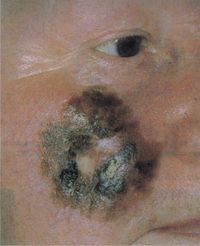

سرطان الخلية القاعدية. Note the pearly appearance and telangiectasia.

A سرطان الخلية القاعدية basal cell carcinoma، هو أحد أكثر أنواع سرطان الجلد شيوعاً.

سرطان الخلية القاعدية

سرطان الخلية القاعدية Basal Cell Carcinoma، ومن مرادفاتها الورم القاعدي basaloma. ولا تعد هذه السرطانة شديدة الخباثة لعدم إحداثها انتقالات سرطانية بعيدة لكنها تتصف بغزوها الموضعي البطيء وتخريبها للنسج التي تنمو عليها. وهي أكثر الأورام الجلدية السرطانية مصادفة، لا تصيب الأغشية المخاطية. كما ويندر مشاهدتها عند العرق الأسود. غالباً ما تبدأ هذه السرطانة بالظهور بعد العقد السادس من العمر، وأكثر ما تشاهد على المناطق المعرضة للضياء وخاصة الأجزاء العلوية من الوجه.

لهذه السرطانة أشكال سريرية متعددة منها العميق الذي غالباً ما يكون صغيراً ومتقرحاً ومنها السطحي الذي غالباً ما يكون متعدداً، ونادراً ما يتقرح. ومنها الشكل المصطبغ والمصمت والكيسي والشكل القشيعي.

يكون مآل هذه السرطانة جيداً إذا ما عولجت باكراً، لكن مآل السرطانة المهملة، التي قد تغزو النسج العميقة كالعضلات والغضاريف والعظام، محتفظ به.

يتوقف علاج هذه السرطانة على درجة انتشارها وعمر المريض وتتم المعالجة حالياً بإحدى المعالجات التالية: استئصال جراحي واسع أو تخثير كهربائي أو معالجة بأشعة X أو بالبرودة.